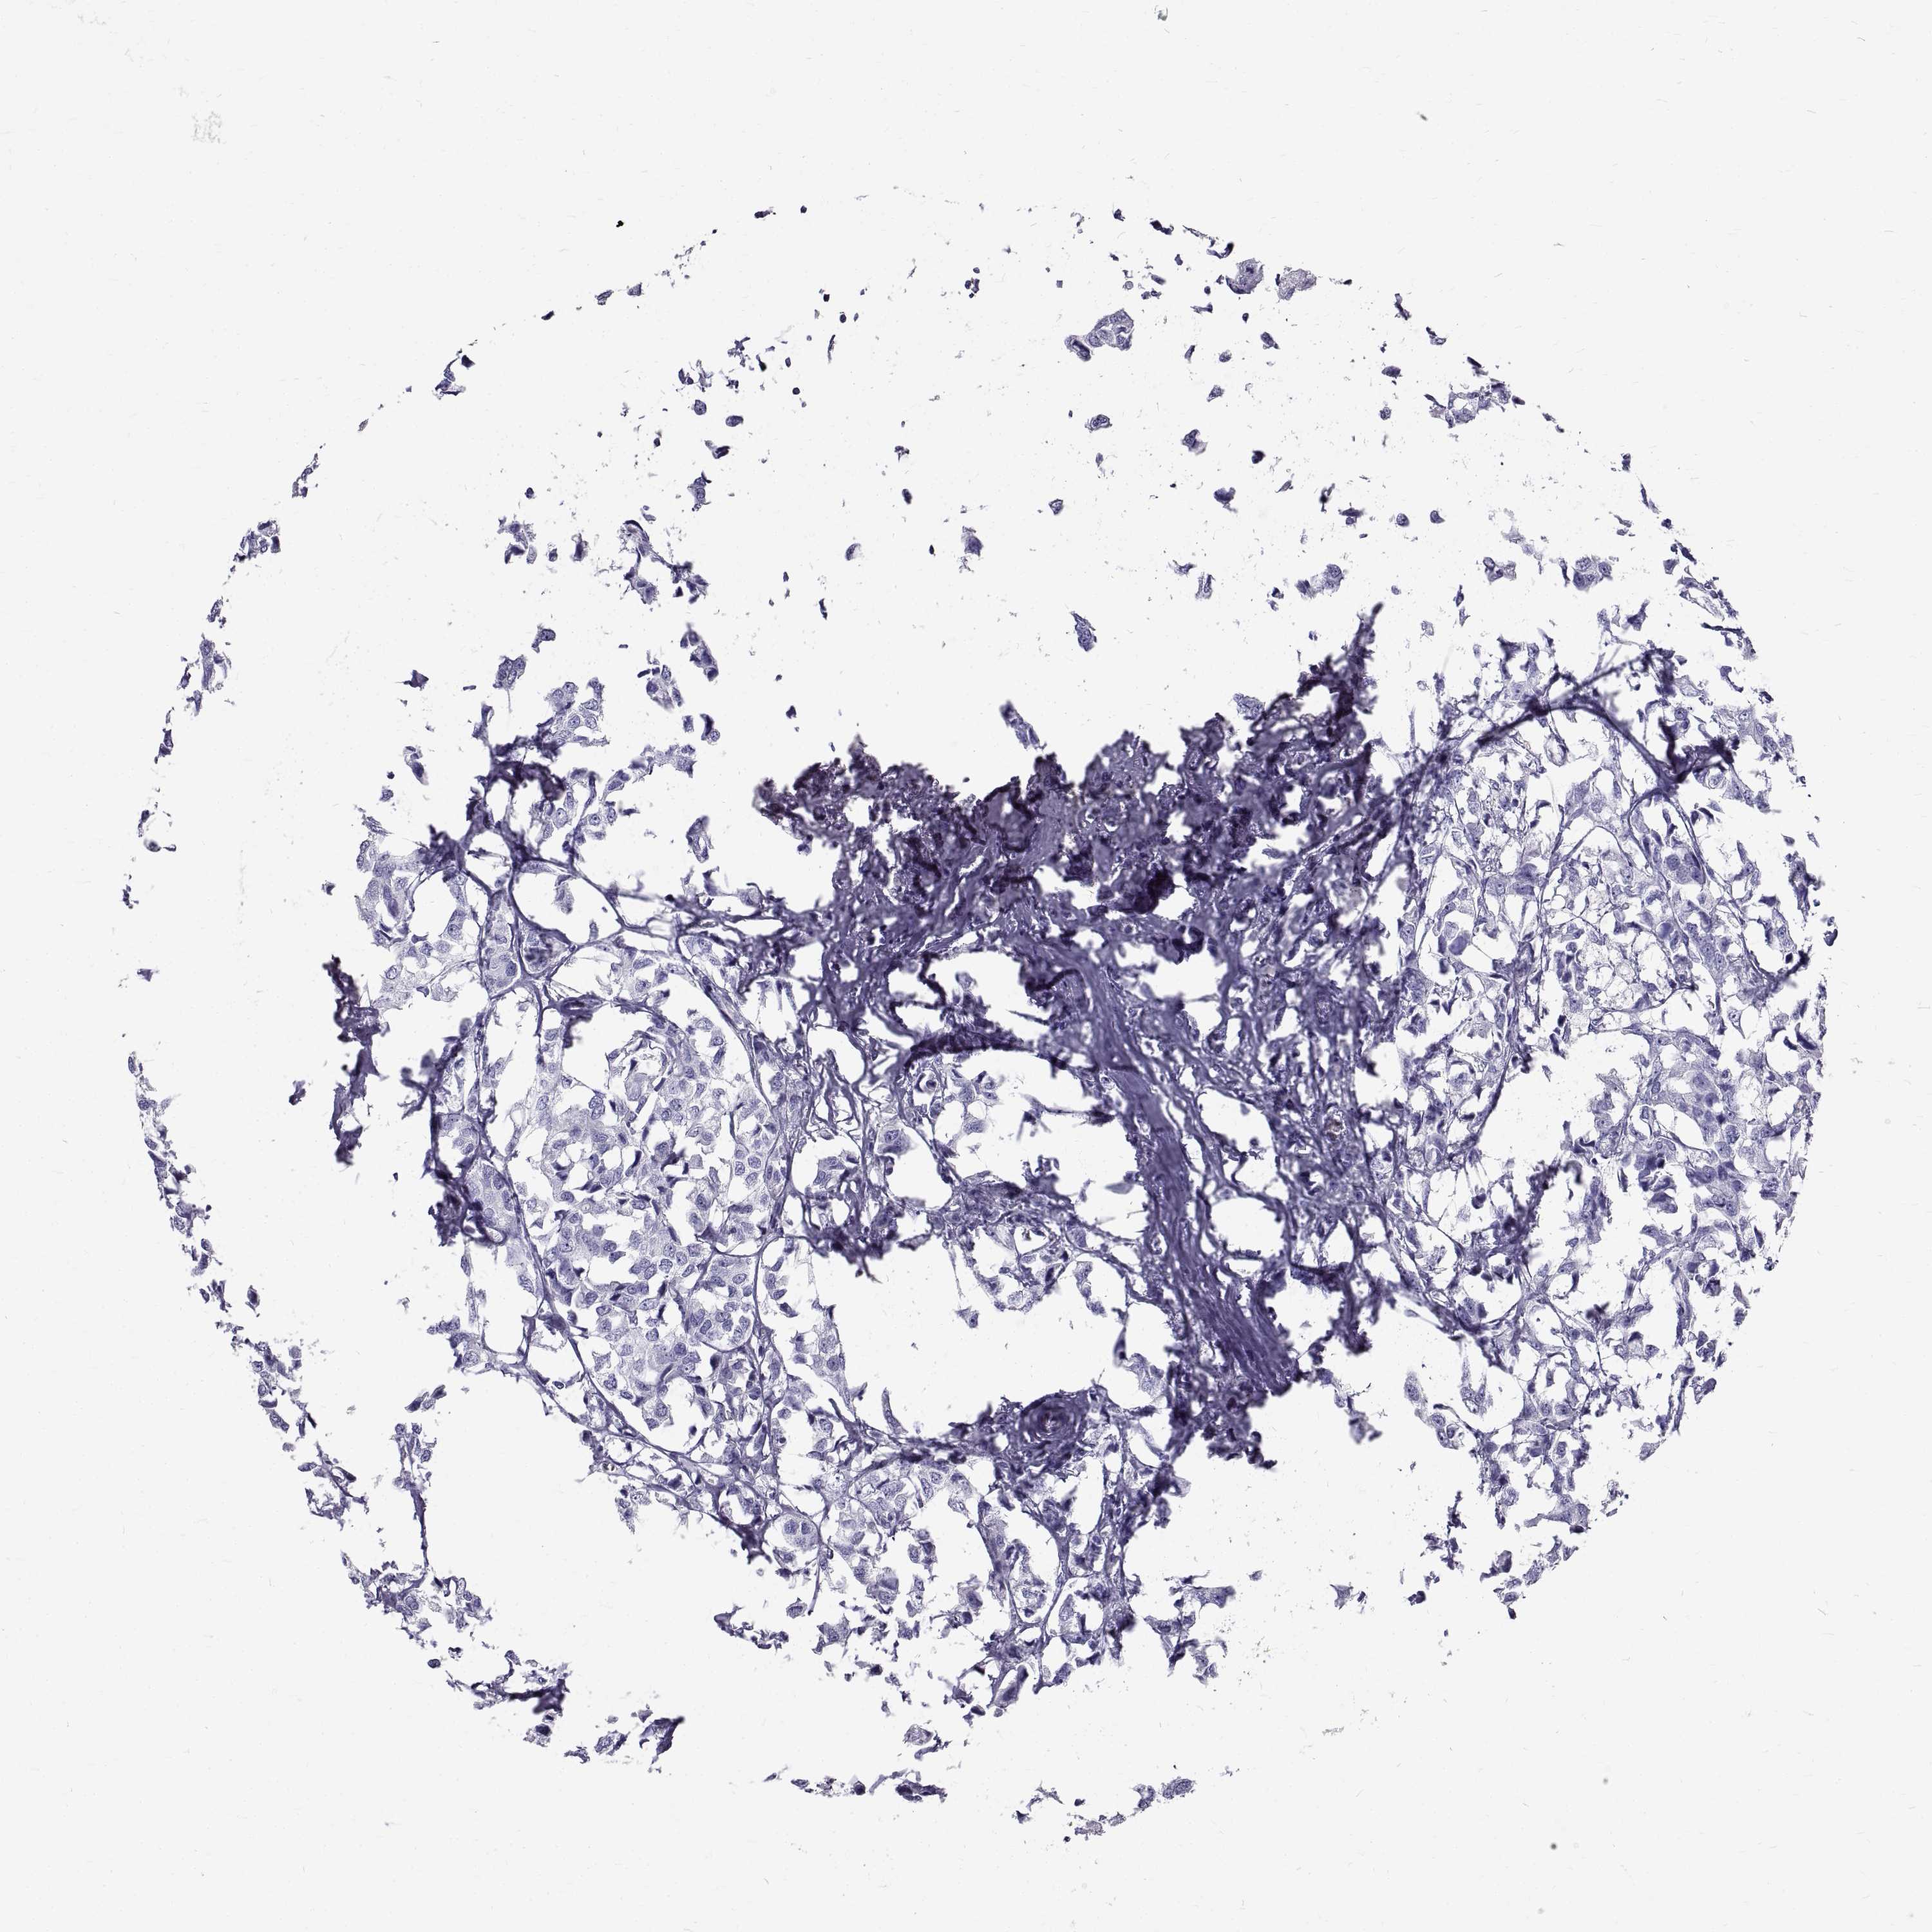

BRCA TCGA BRCA VALIDATION PROTEIN EXPRESSION

Breast cancer

Human cancer